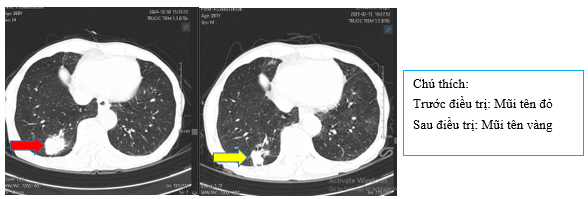

- Chụp CT bụng sau điều trị:

Hình 9: So sánh phim chụp CT bụng trước điều trị nốt tuyến thượng thận ~11mm (mũi tên đỏ) đã giảm nhẹ kích thước sau điều trị còn ~9mm (mũi tên vàng)